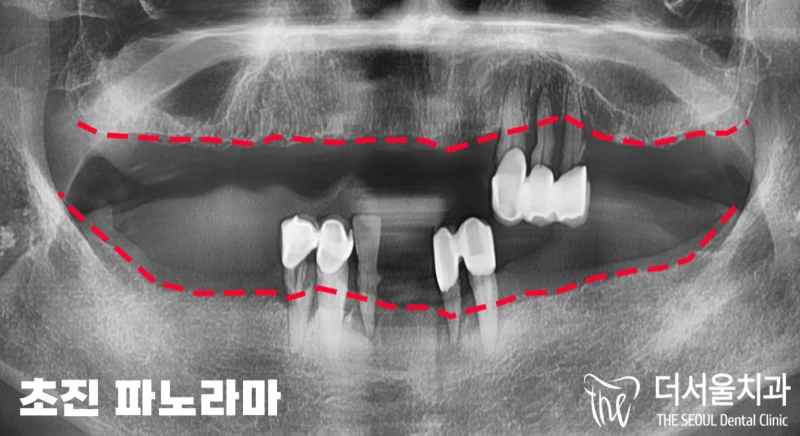

반갑습니다. 판교역 더서울 치과 쌍둥이 박현성 원장입니다. 오늘 보여드릴 임플란트 케이스는 조금 특이했다고 말씀드릴 수 있는데요. 환자분께서는 초등학교를